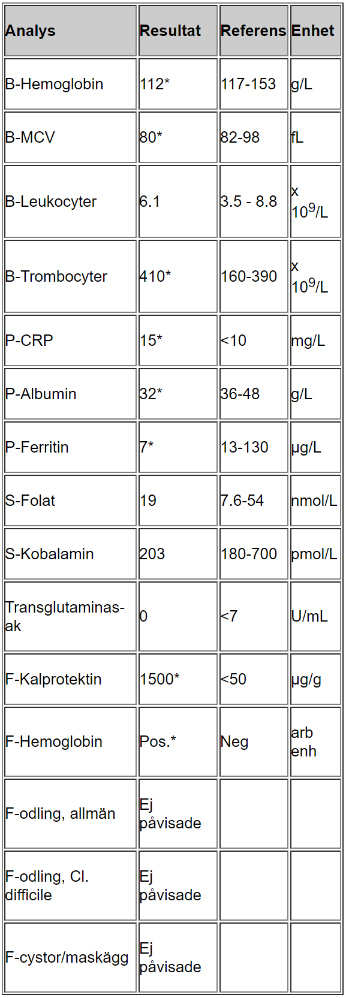

Tolka proverna

- B-hemoglobin, MCV, ferritin lågt vilket tyder på inflammation/blödning, eventuellt problem med näringsupptag

- Trombocyter högt som kompensation för blödning

- CRP lite högt tyder på låggradig inflammation

- Albumin lågt kan tyda på inflammation (omvänd markör)

- F-Kalprotektin högt tyder på IBD

- F-hemoglobin tyder på att det pågår blödning i tarmen, hon har inte uppmärksammat det själv vilket tyder på blödning något mer proximalt i tarmen